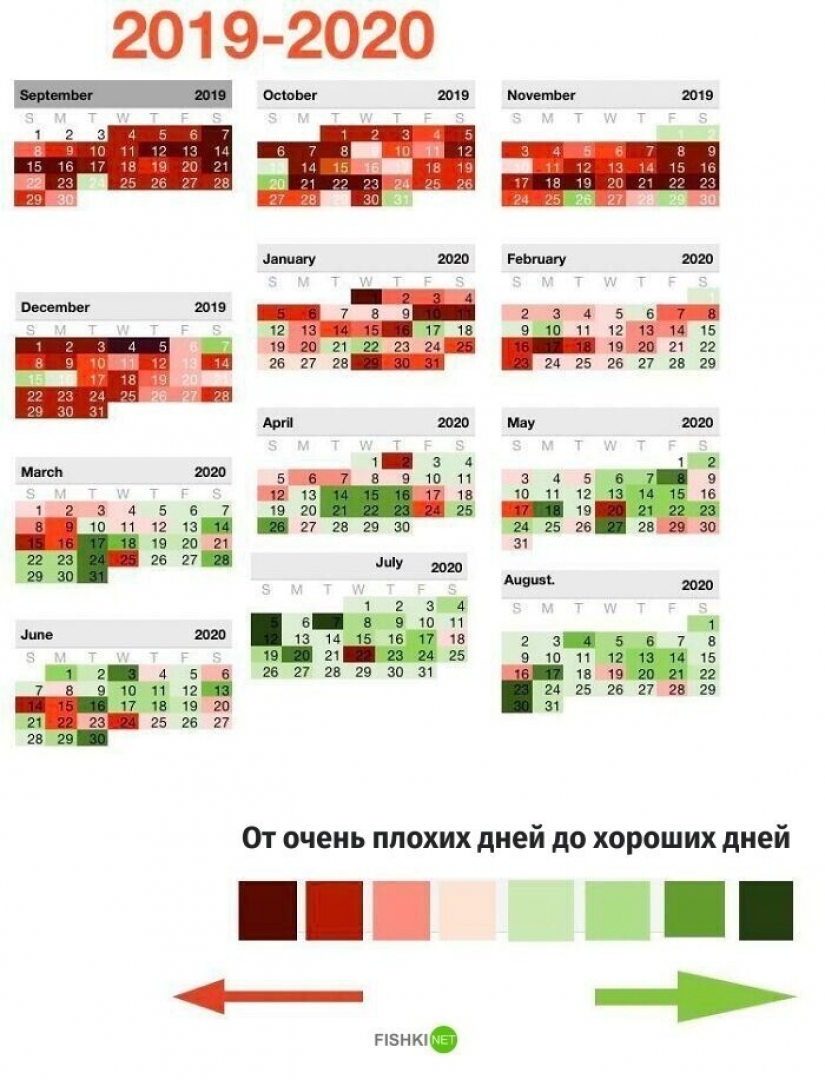

"A year ago I was hospitalized due to a suicide attempt. Then I decided that I wanted to be healthier and happier. Here's my calendar, where I noted the dynamics of depression. Don't give up!"